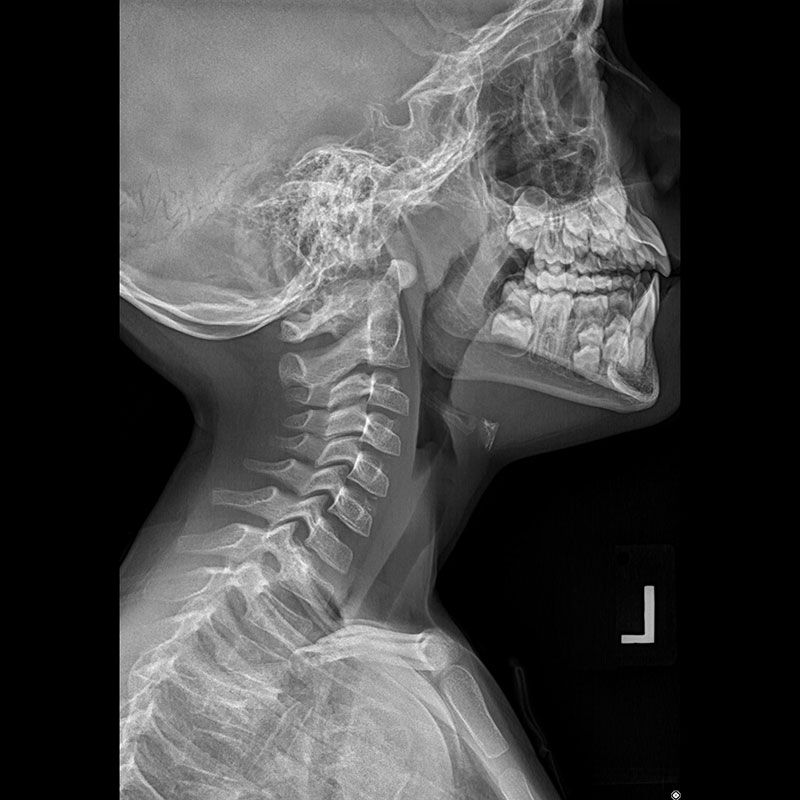

Оправившись от минутного изумления, Рентген начал изучать обнаруженное явление и новые лучи, названные им Х-лучами. Оставив футляр на трубке, чтобы катодные лучи были закрыты, он с экраном в руках начал двигаться по лаборатории. Оказывается, полтора-два метра для этих неизвестных лучей не преграда. Они легко проникают через книгу, стекло, станиоль… А когда рука ученого оказалась на пути неизвестных лучей, он увидел на экране силуэт ее костей! Фантастично и жутковато! Но это только минута, ибо следующим шагом Рентгена был шаг к шкафу, где лежали фотопластинки: увиденное нужно было закрепить на снимке.

8 ноября 1895 года Рентген заметил, что, когда он экранировал трубку плотным черным картоном, зеленый флуоресцентный свет заставлял светиться платинобариевый экран на расстоянии девяти футов — слишком далеко, чтобы реагировать на катодные лучи, как он их понимал. . Он определил, что флуоресценция была вызвана невидимыми лучами, исходящими из трубки Крукса, которую он использовал для изучения катодных лучей (позже признанных электронами), которые проникали через непрозрачную черную бумагу, обернутую вокруг трубки. Дальнейшие эксперименты показали, что этот новый тип луча способен проходить через большинство веществ, включая мягкие ткани тела, но оставляет кости и металлы видимыми. Одной из его первых фотопластинок, сделанных во время его экспериментов, была пленка руки его жены Берты, на которой было ясно видно ее обручальное кольцо.